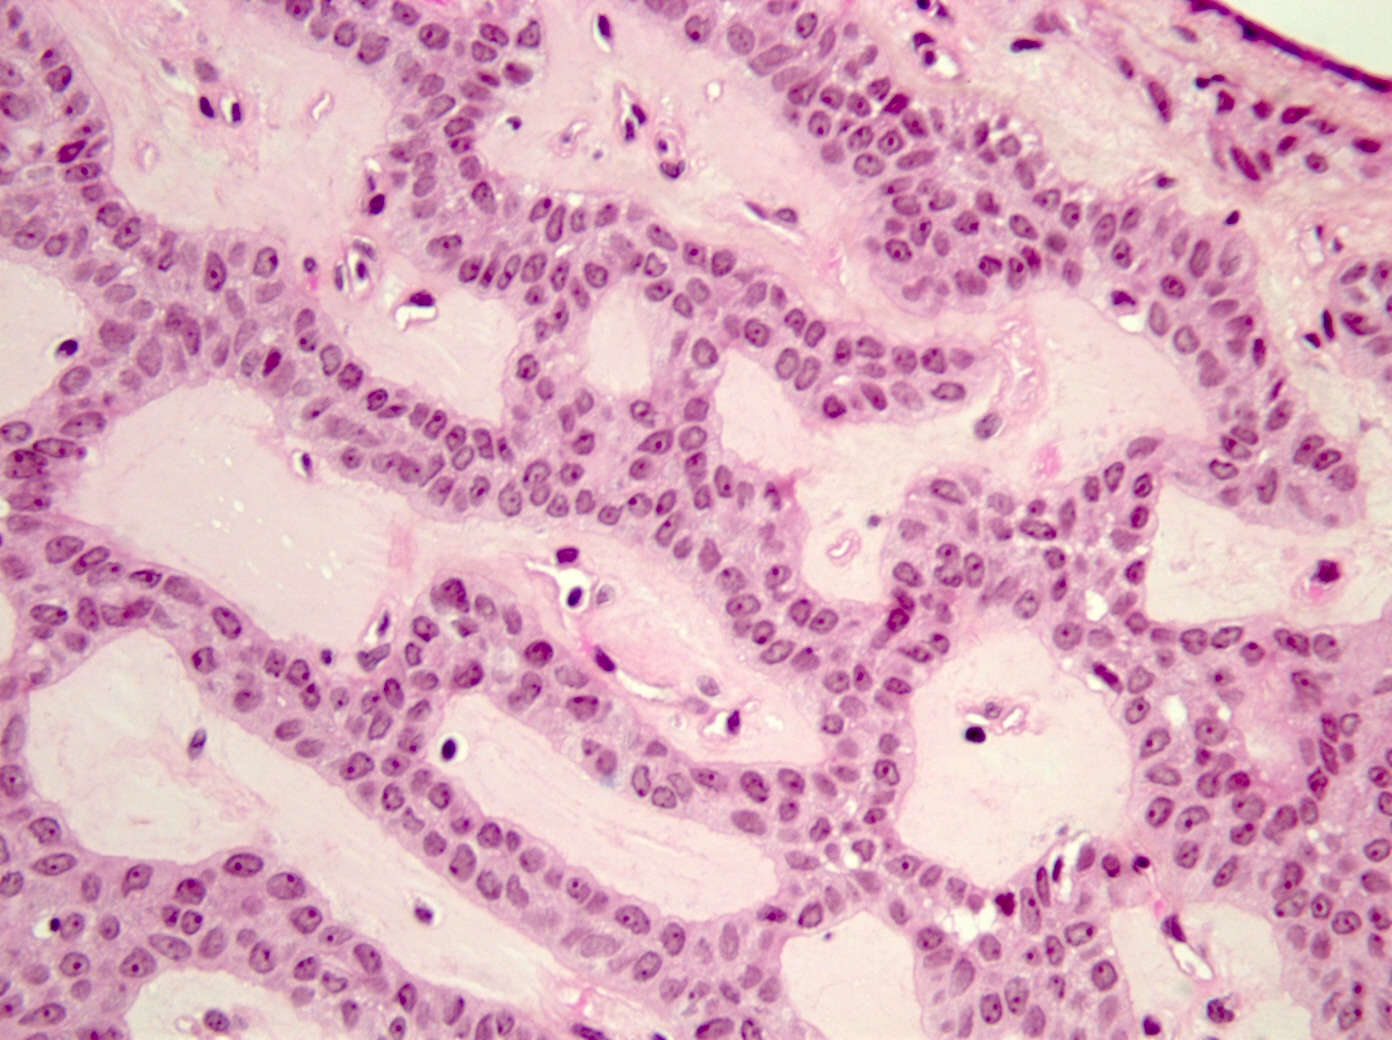

Microscopic (histologic) description

- Bilayered strands or ribbons or anastomosing cords or branching tubules

- Canalicular to cystic spaces between the cell strands; trabecular features

- Lack of an outer layer of myoepithelial cells

- Beading pattern, club ended cords

- Tumoral columnar or cuboidal cells, foci of basaloid cells

- Amphophil to eosinophilic cytoplasm, apocrine / oncocytic

- Round to elliptical, uniform nuclei, focally nucleoli, basophilic chromatin, rare to absent mitoses

- Mucous / mucinous metaplasia (Head Neck Pathol 2015;9:181)

- Microliths, tyrosine crystals, morules and squamous balls (intraluminal) (J Craniomaxillofac Surg 2017;45:1754, Head Neck Pathol 2015;9:181, Histopathology 1999;35:502)

- Well vascularized, loose stroma; possibly sclerotic; perivascular eosinophil cuffs

Microscopic (histologic) images